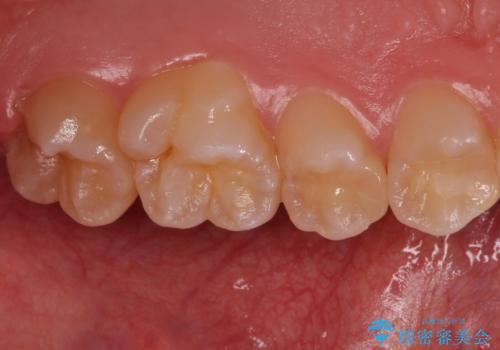

歯と歯の間の虫歯 セラミックインレーでの治療

- 検査の結果、歯と歯の間に大きな虫歯が確認されました。

セラミックでの治療をご希望されたため、セラミックインレーでの治療を行いました。

外から見て虫歯がないように見えても実は歯の中で大きく広がっていた、というケースは多く見受けられます。

症状なく進行していくことも少なくないため、定期的な検査はとても重要になってきます。

今回は残せる歯の厚みが十分確保できたため、インレーでの修復処置となりました。